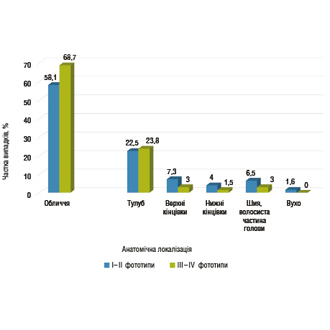

Віково-орієнтована модель стратифікації ризику базальноклітинної карциноми: взаємозв’язок віку, фототипу шкіри та анатомічної...

Автор:Ковтун Л.О. -